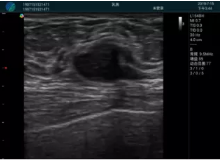

腺體內(nèi)部清晰顯示一低回聲塊影,形態(tài)不規(guī)則,邊界模糊,邊緣呈毛刺狀,內(nèi)部見砂礫樣鈣化

M20引導下穿刺活檢術(shù)

M20引導下平面內(nèi)穿刺取出的腫塊組織